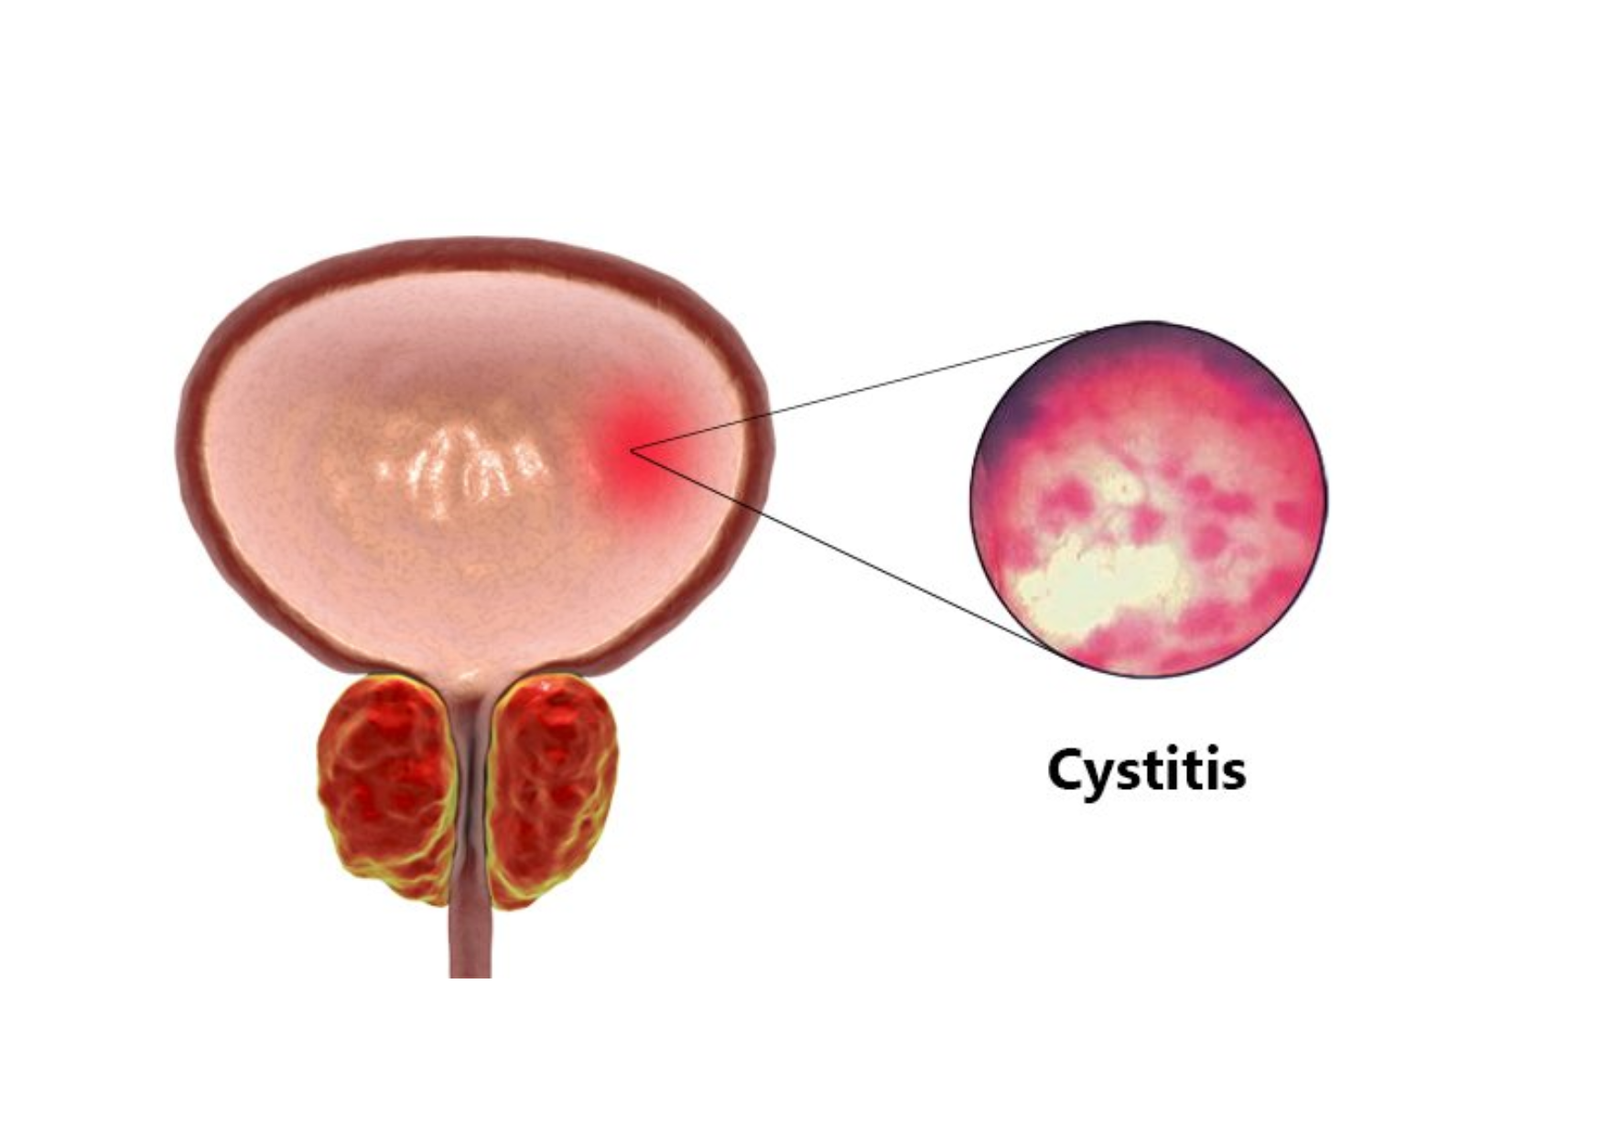

The vast majority of urinary tract infections present as uncomplicated cystitis, primarily affecting the lower urinary tract in healthy adult females.

A complicated urinary tract infection indicates that underlying anatomical, functional, or systemic factors are actively compromising the body’s ability to clear the bacterial pathogen. In these elevated risk scenarios, the infection can rapidly ascend from the bladder, travel upward through the ureters, and aggressively invade the renal parenchyma.

Severe Cystitis | Diffuse or focal thickening of the muscular bladder wall exceeding three millimeters when the bladder is fully distended. The sonogram may also reveal mobile, echogenic debris floating within the luminal fluid. | Confirms advanced lower urinary tract inflammation, highly common in chronic, treatment resistant infections. |